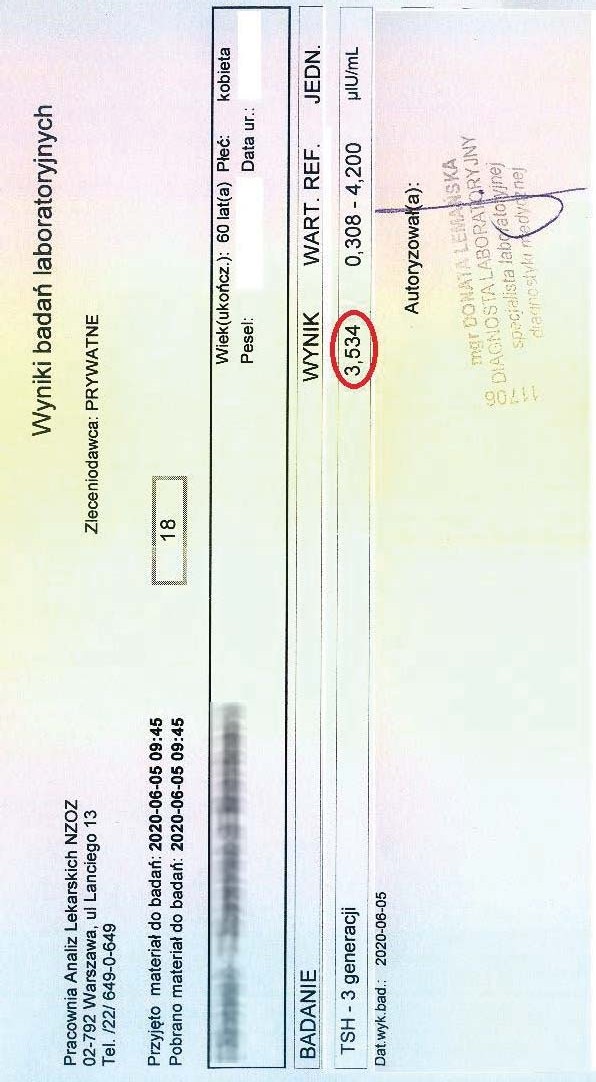

PRZYKŁAD EFEKTU PREPARATU NA NIEDOCZYNNOŚĆ TARCZYCY

Kobieta lat 59 z niedoczynnoscią tarczycy, bez przyjmowania lewotyroksyny. Kobieta przyjmowała preparat przez okres ponad 3 miesięcy. Przy zachowaniu naturalnego cyklu komórkowego i stałemu stymulowaniu mitochondriów osiągneła następujące wyniki kuracji:

Po zaobserwowaniu znacznej poprawy w ogólnym samopoczuciu, kobieta postanowiła wykonywać badania ze zwiększoną częstotliwością oraz kontrolę prób wątrobowych.

Po kolejnych dwóch miesiącach kobieta ponownie wykonała badania. Widoczne są: spadek TSH, obniżenie stanu zapalnego jak i spadek markeru wątrobowego GGTP.

Sukcesywnie co 2 miesiące można zaobserwować stały spadek parametrów zarówno wątroby jak i tarczycy. Kolejne badania potwierdzały dalszy spadek parametrów.

Po ponad roku kuracji badania wykazały dalszy postęp wycofania autoimmunologi tarczycy, potwierdzone również badaniem USG narządu.

Preparat wpływając na odbudowę mitochondriów zapewnił podłoże energetyczne do produkcji hormonów i odbudowy narządu. Brak ingerencji farmakologicznej wykazuje skuteczność nawet w podeszłym wieku, gdzie regeneracja jest wolniejsza a reakcje anaboliczne w znacznym stopniu spowolnione. Można zaobserwować także działanie ogólnoustrojowe obserwując spadek markeru wątroby, co jasno wykazuje poprawę funkcjonowania całego organizmu.